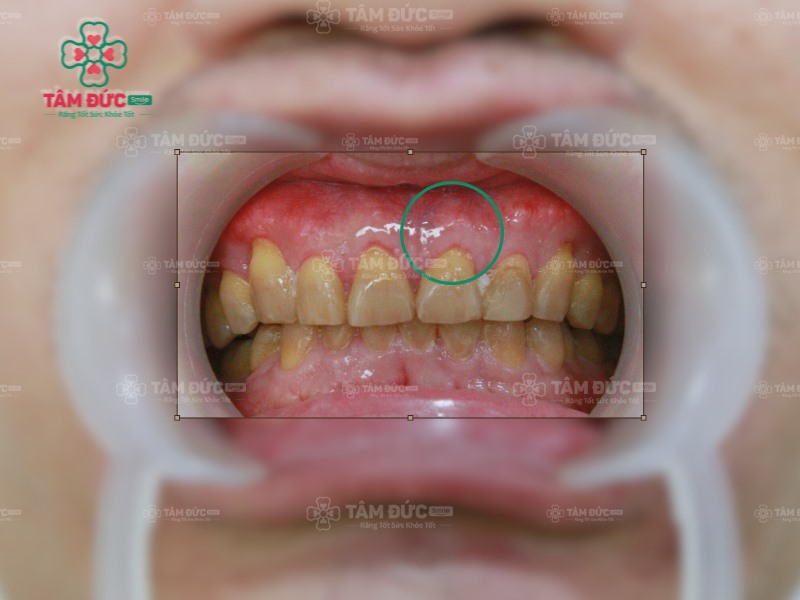

Viêm lợi là một trong những bệnh lý viêm nhiễm ở khoang miệng, làm nướu sưng đỏ và chảy máu. Tình trạng này bắt nguồn từ sự tấn công của vi khuẩn trong mảng bám, hoặc do cao răng tồn tại trong thời gian dài gây ra. Khi không được điều trị đúng cách, viêm lợi sẽ nhanh chóng tiến triển thành viêm nha chu.

Viêm lợi sưng đỏ nhanh chóng tiến triển thành viêm nha chu